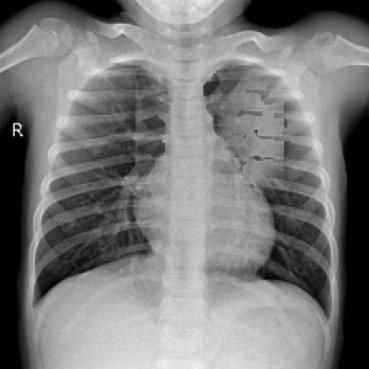

The impact of position guidance is visualized through the Class Activation Mapping (CAM) in Fig. 3. In the first row, the entire lung view fails to detect anomalies in the left region. However, specific views focused on the left, upper, and lower sections of the lung successfully identify these anomalies. In the second row, the left lung view detects anomalies that are missed in the entire lung view. These outcomes indicate the importance of utilizing diverse position prompts.